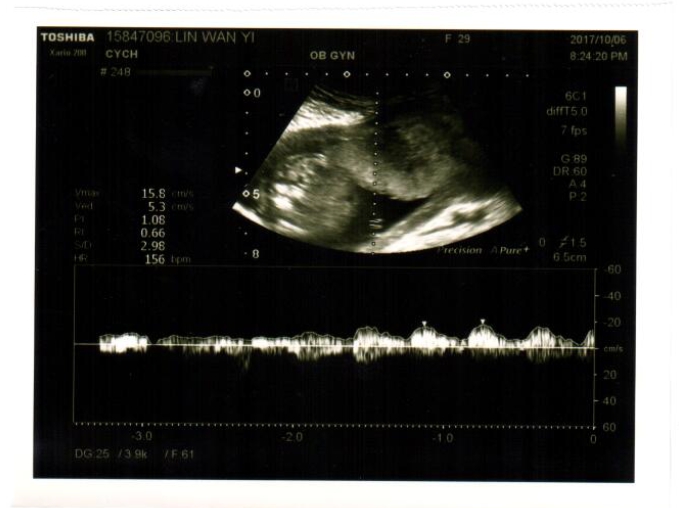

「胎兒看起來偏小,有做過什麼檢查嗎?羊膜穿刺、非侵入性晶片....」

產檢結束,我腦海中不斷想著王醫師說胎兒偏小那段話,回想去懷孕以來因為工作忙碌和交際應酬都不太早睡,又有時忙到沒時間吃飯,不禁擔心了起來,開始上網查訊胎兒偏小的資訊(強迫症上身了!)

除了睡眠和飲食以外,胎兒偏小和生長遲緩的狀況大部分似乎發生在唐氏症寶包身上,又胎動較少不明顯也是其一觀察的因素,孩子的胎動和上胎姐姐一樣,我並不太常能感受到強烈的胎動...天哪,我簡直要把自己嚇傻了,尤其回想王醫師問羊膜穿刺和非侵入性晶片等檢查,我一樣都沒做,且高層次超音波是測不出染色體異常的,在這次產檢之後我真的有點擔心,但又不時要告訴自己放寬心,順其自然。